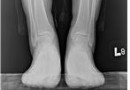

발목 관절염

발목 관절염 발목관절염은 외상에 의해 인대손상이나 연골 손상 후 이차적으로 발생하는 경우가 가장 많으며 통풍이나 류마티스와 같은 전신질환의 합병증으로 인해 발생하는 경우도 있습니다. 발목 관절 주위에 부종과 통증, 압통을 동반을 하며 보행 시 통증이 지속이 되는 양상을…